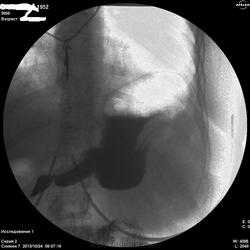

По-желудку - расположен косопоперечно, в гипертонусе. Впечатление не полного тугого наполнения. На большой кривизне могут быть и складки, плохо видно. На малой кривизне похоже на 2 ниши, ширина которых преобладает над глубыной, могут быть онкологические, но опять же куда они деваются на последнем снимке... Пилорический отдел либо конически сужен, либо не наполнен адекватно. В общем, можно просто предположить, либо это язвеная болезнь "хроническая" (отсюда деформация желудка и все остальное), либо это онкология (лимфома к примеру). Либо вообще такую картину дает гипертонус, усиленная перистальтика и малое количество контраста. Предложил бы искусственную гипотонию и бария не менее 200 мл.

Жалоб конкретных нет(так,что-то ноет).Еть отрывки кинопетли лёжа,но сегодня не смогу показать.Первый кадр здесь-стоя,потом-с поворотами налево и направо.Я собственно снимки не делаю,пишу кино.В "последующих сериях" деффект сохранялся,на компрессию не реагировал.

Первые три-в орто.Последний-лёжа.